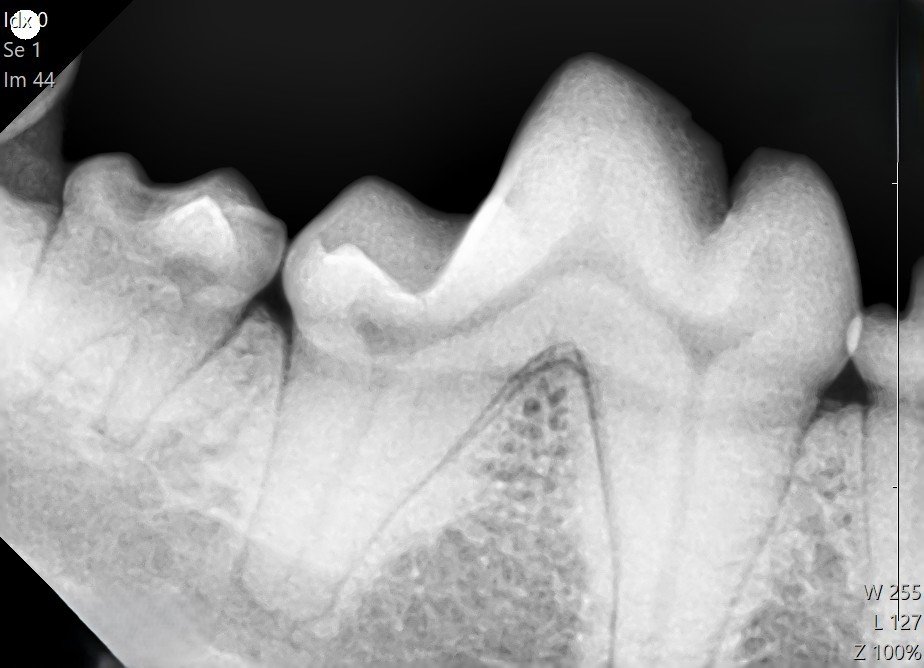

①歯科用レントゲン装置により、現在の歯の状態を確認する。

これにより、目に見えない歯根部の評価をしっかりと行い、残せる歯をしっかり残すような処置が可能となります。 (歯科レントゲン撮影はオプションとなります)

全ての歯を部位に分けてレントゲン撮影を行います。

今回は全体的に歯周病の進行は見られなかったため、まだまだ歯は温存できると判断しました。